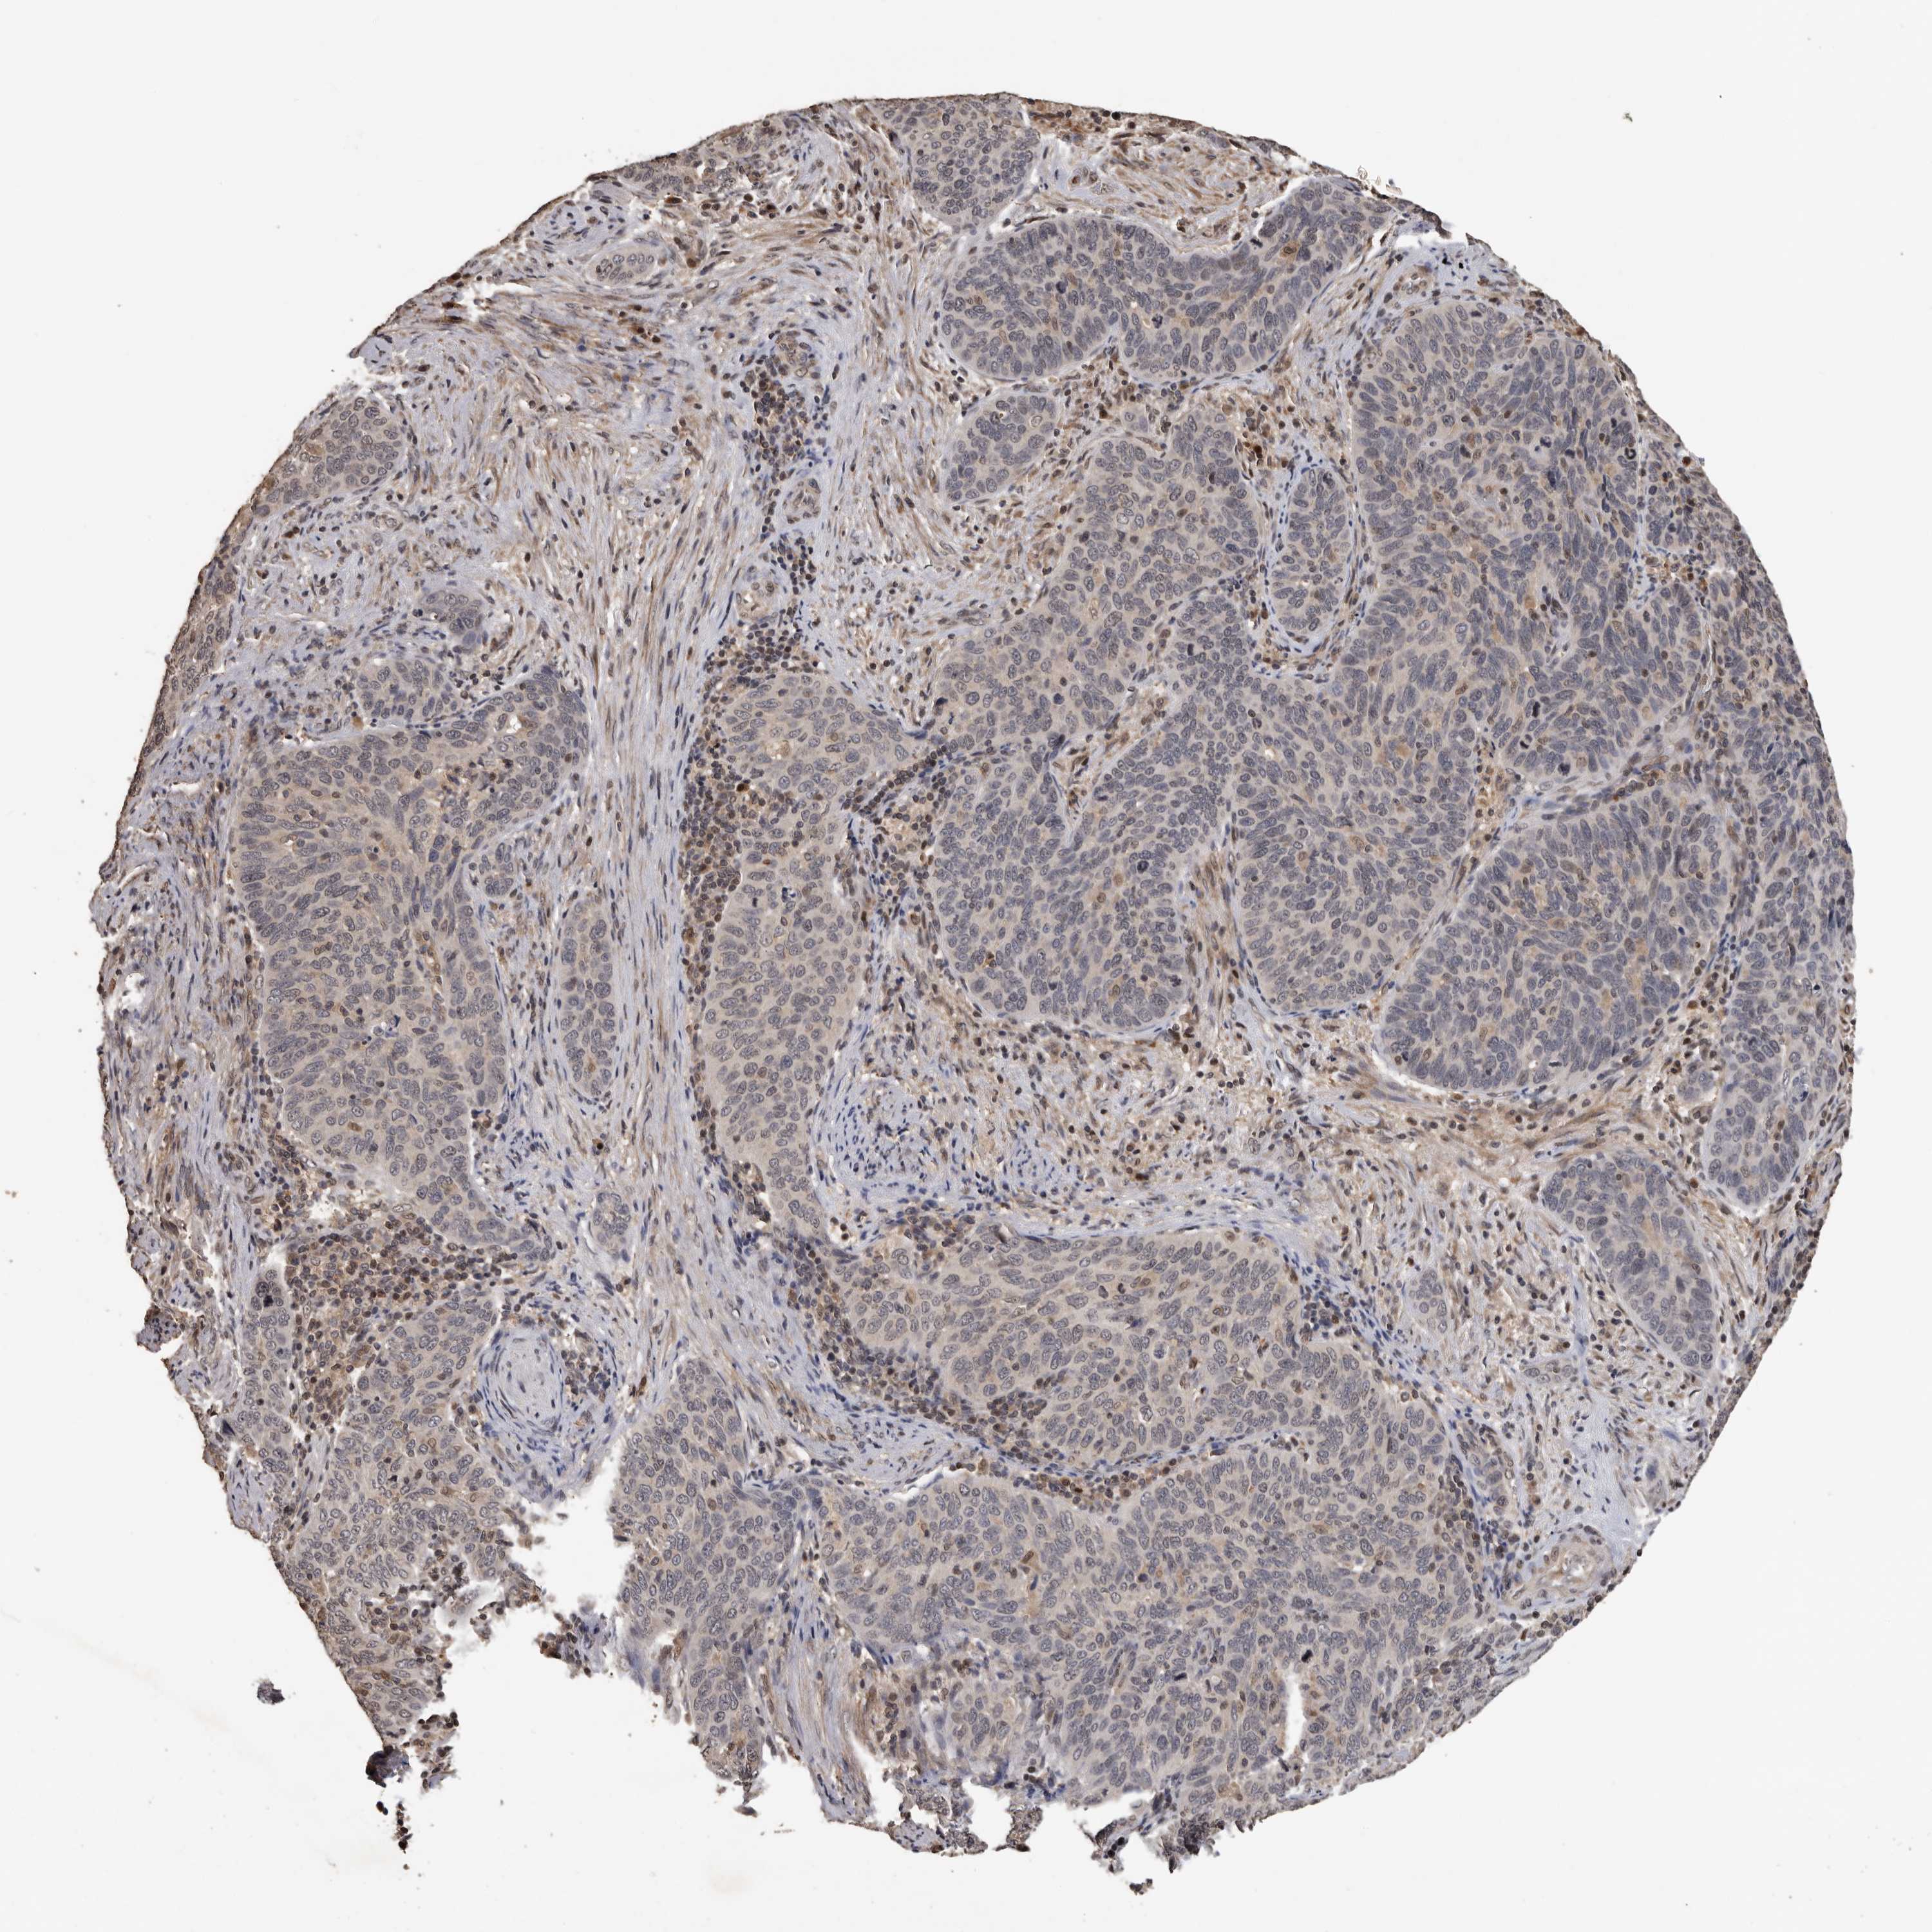

CERVICAL CANCER - Protein expressioni

A mouse-over function shows sample information and annotation data. Click on an image to view it in a full screen mode. Samples can be filtered based on level of antibody staining by selecting one or several of the following categories: high, medium, low and not detected. The assay and annotation is described here.

Note that samples used for immunohistochemistry by the Human Protein Atlas do not correspond to samples in the TCGA dataset.

Antibody stainingi

Antibody staining in the annotated cell types in the current human tissue is reported as not detected, low, medium, or high, based on conventional immunohistochemistry profiling in selected tissues. This score is based on the combination of the staining intensity and fraction of stained cells.

Each image is clickable and will lead to virtual microscopy that enables deeper exploration of all samples and also displays staining intensity scores, fraction scores and subcellular localization as well as patient and tissue information for each sample.

Antibody HPA023081

Antibody HPA023103

Antibody HPA024795

Squamous cell carcinoma, NOS